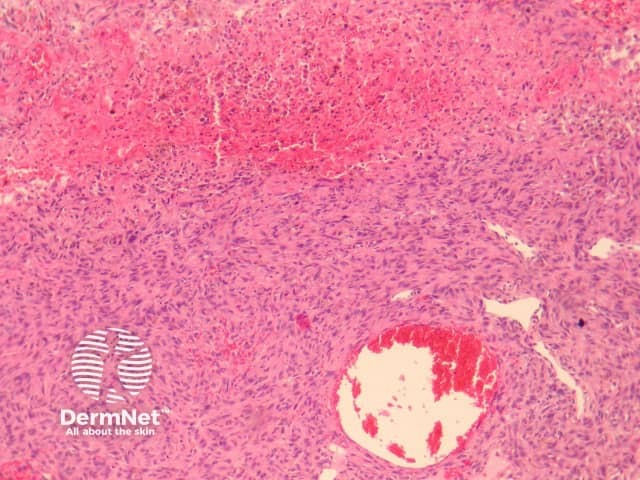

The clinical presentation of aneurysmal dermatofibroma is a rapidly growing blue-brown nodule. Periods of rapid growth are secondary to haemorrhage into the lesion. These tumours have a high recurrence rate and there is a report of aneurysmal dermatofibroma with regional lymph node involvement.

Histologically, there are cleft-like haemorrhagic spaces within the centre of the aneurysmal dermatofibroma that mimic vessels but lack an endothelial lining. The tumour itself tends to be fairly cellular (figure 7, 8). Haemosiderin deposition may be an additional feature. Aneurysmal dermatofibroma may be mistaken for a vascular tumour, however, clues to the diagnosis include surrounding features of dermatofibroma, and endothelial cell markers are positive in normal vessels only and not the aneurysmal spaces.

Figure 7

Figure 8